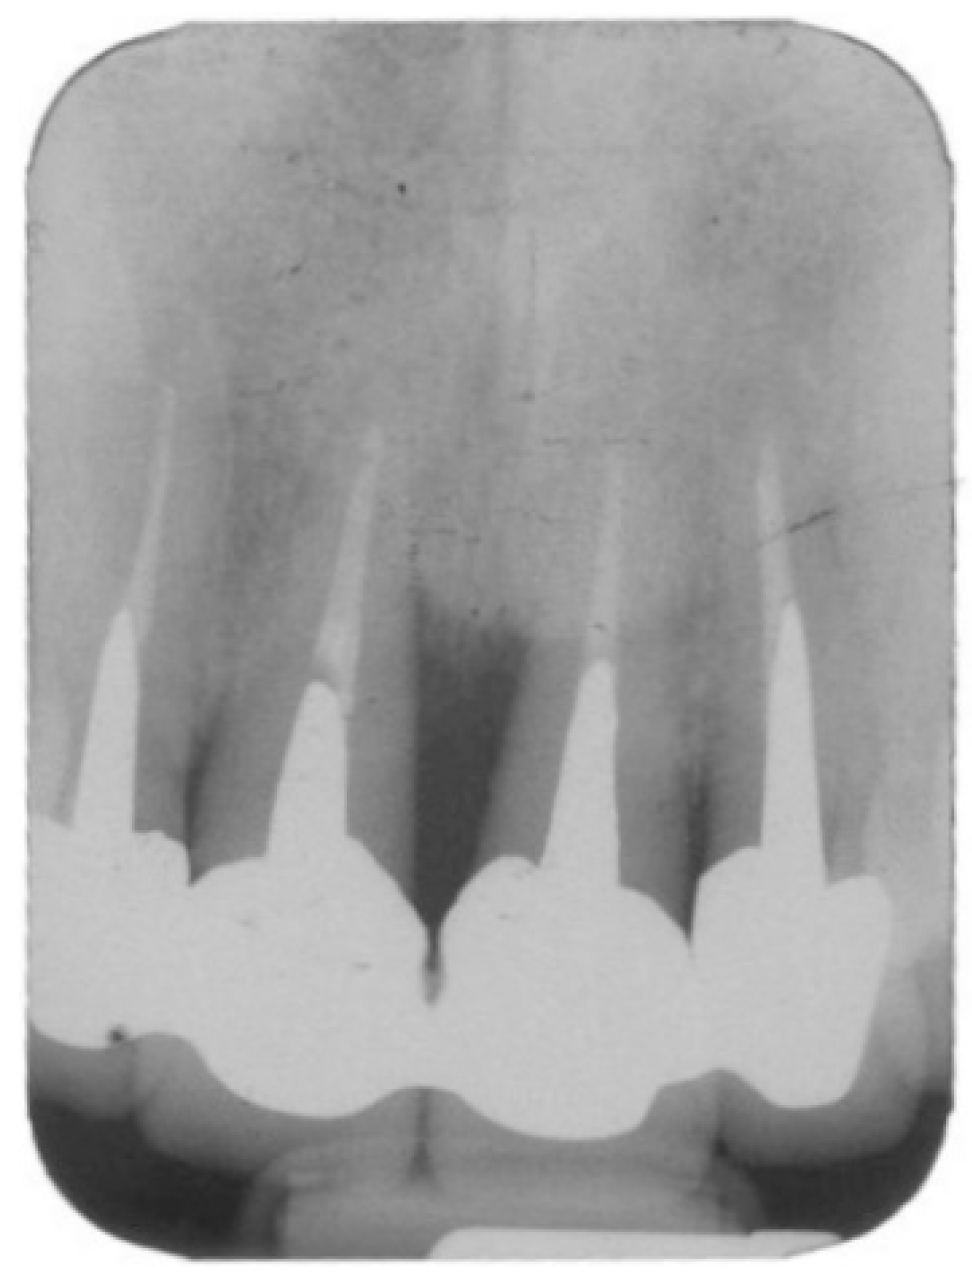

A detailed pre-surgical evaluation that comprised a full-mouth periodontal chart and an occlusal analysis was carried out. Data on smoking habits, periodontal diagnosis, and reason for extraction were obtained and recorded prior to a decision of extraction and surgery. The cause-related therapy included oral hygiene instructions and scaling and root planning when indicated, followed by additional periodontal therapy aiming to reduce periodontal probing depth and bleeding upon probing. Periapical radiographs were obtained before (Figure 1) and immediately after implant placement, six months later, once yearly, and at the time of data collection (1–7 years after bridge installation). A preoperative computed tomogram (CT) was obtained to evaluate the height and width of the alveolar process. Special attention was given to the existence of any bone undercuts, the location of the roots to be extracted, the presence of periapical/peri radicular pathologies, and the location of the incisive foramen. Premedication with 875 mg amoxycillin–clavulonate potassium (Augmentin, Smith Kline, Brentford, UK) was given one hour before surgery. The patients performed a one-minute rinse with chlorhexidine 0.2% (Tarodent mouthwash) solution before undergoing the procedure.

Figure 1.

Periapical radiographs of a 37-year-old nonsmoker woman with hopeless 12–22 teeth due to severe bone loss (patient# 17).